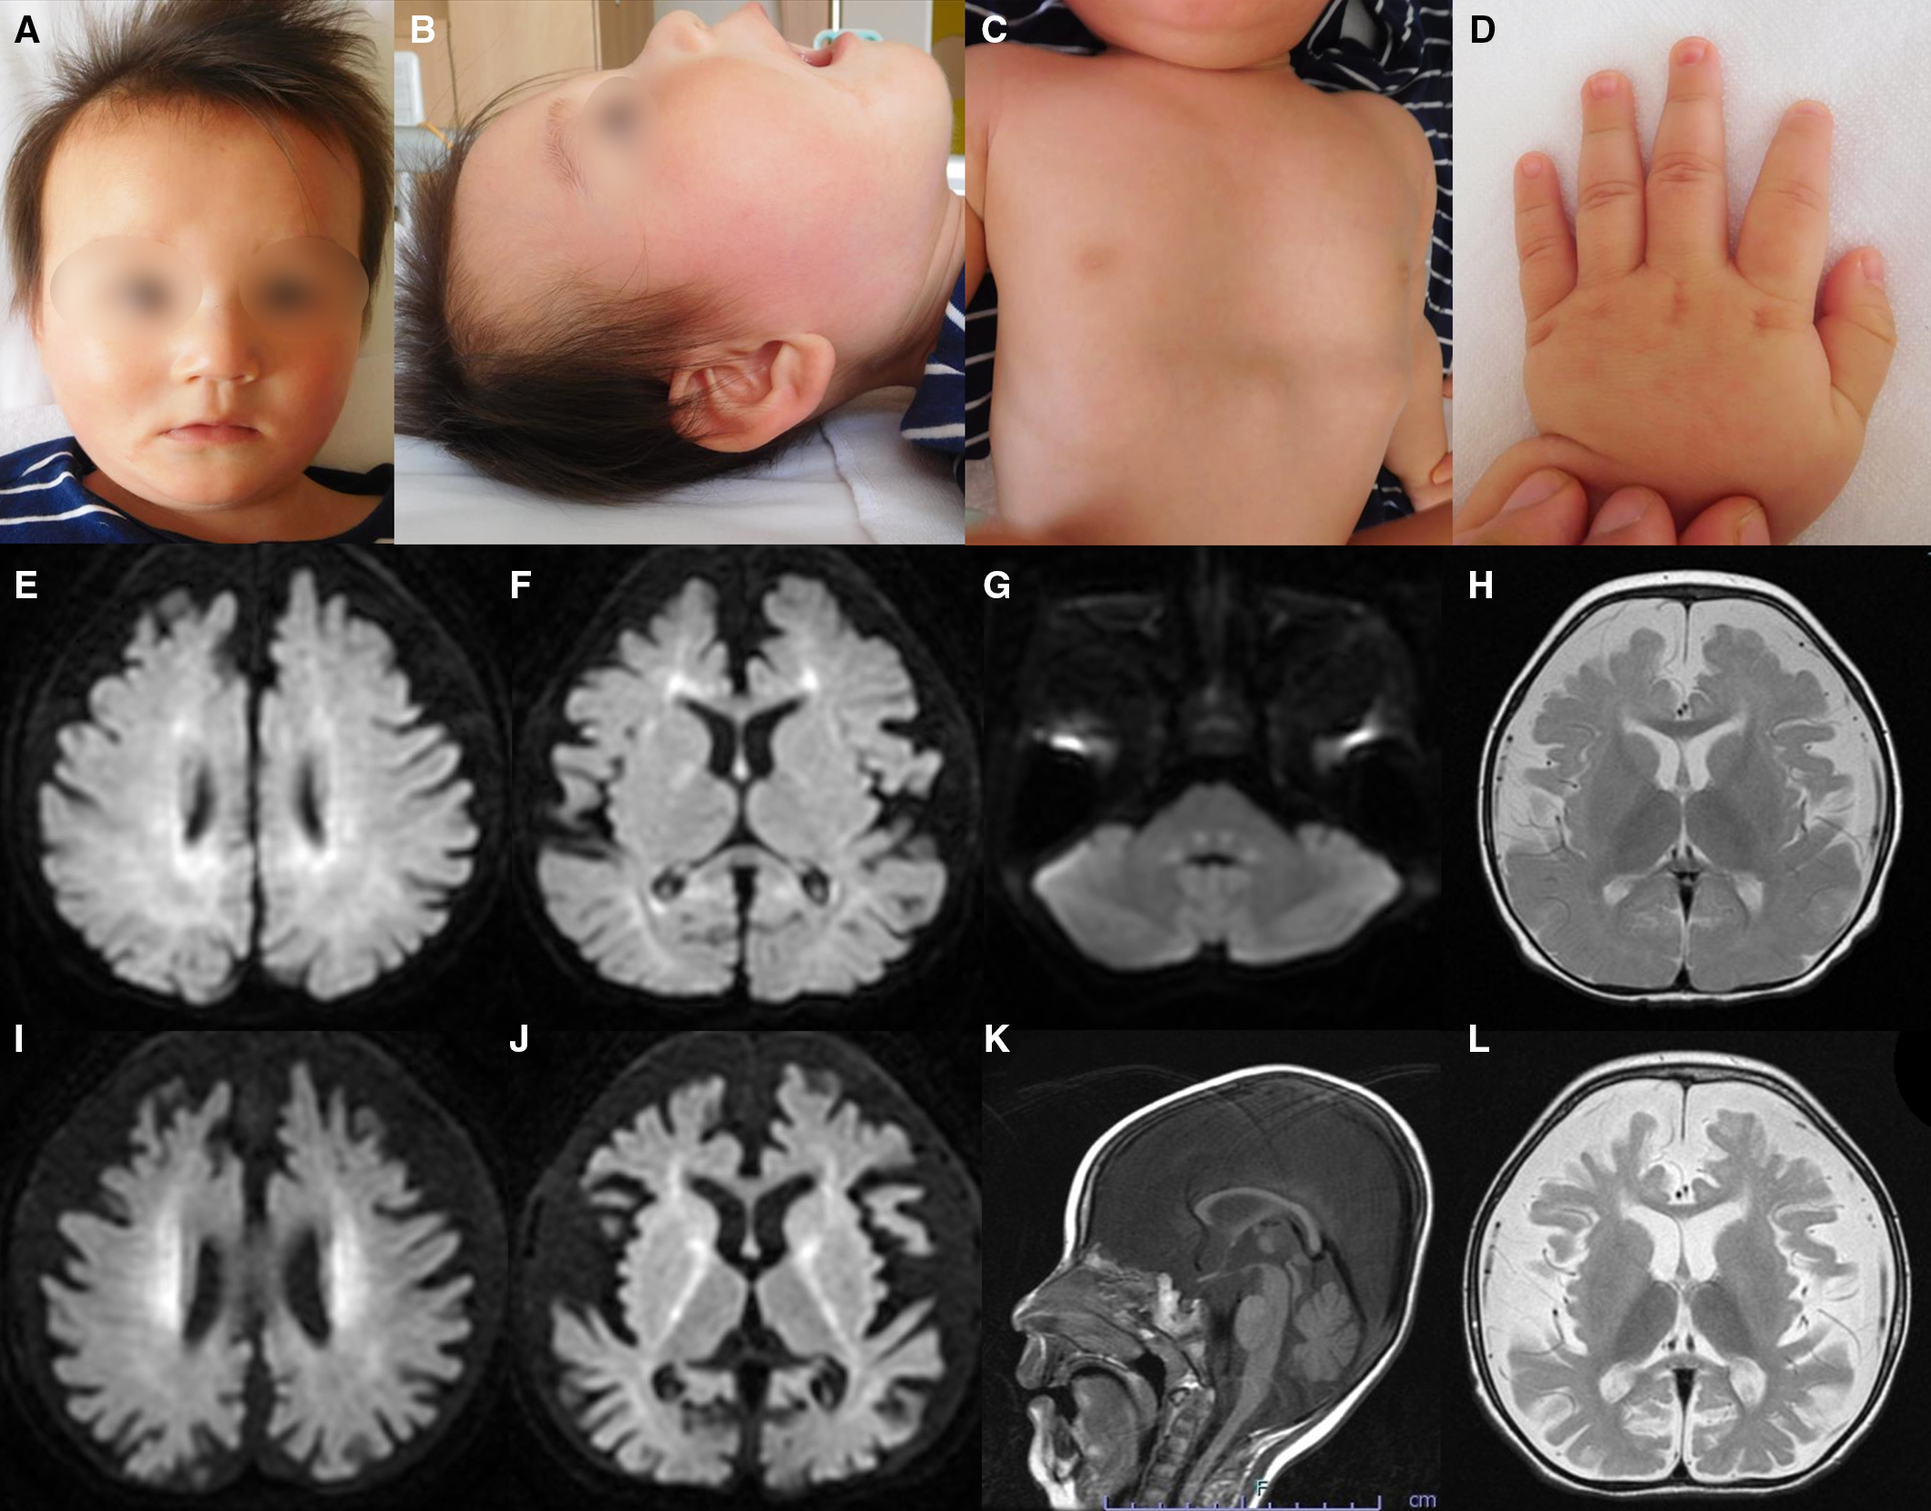

After 40 weeks of gestation without asphyxia, a Japanese boy was born to nonconsanguineous, healthy parents as their first child. His birth weight was 3,450 g [+1.04 standard deviation (SD)], his length was 51.0 cm (+0.90 SD), and his occipitofrontal circumference was 35.0 cm (+1.25 SD). Distinctive facial features such as widely spaced eyes and pointed chin, pectus excavatum, tapered fingers, esotropia, and muscle hypotonia, were noted (Figures 1A–D). He could hold his head up at five months of age and sit with support at eight months of age. At nine months of age, he babbled but could not maintain a sitting position, even with support. At one year and one month of age, antiepileptic drugs were initiated because of the onset of epileptic spasms and focal to bilateral tonic-clonic seizures. His development regressed, losing interest in toys at one year and three months of age and becoming unable to hold his head up at one year and eight months of age. Tube feeding was initiated because of dysphagia and weight loss at two years and one month of age, followed by gastrostomy at three years of age.

Figure 1

Representative clinical findings. (A–D) Photographs of the patient at ten months of age. Widely spaced eyes, epicanthus, left esotropia, medial sparse eyebrow, pointed chin, and thin upper lip vermilion are observed (A, B). Pectus excavatum (C) and tapered fingers (D) are recognized. (E–L) Brain magnetic resonance imaging (MRI) at ten months of age (E–H) and one year and eight months of age (I–L). Axial diffusion-weighted imaging (DWI) demonstrated elevated signal in the bilateral periventricular white matter, deep and subcortical white matter of the bilateral posterior lobe, posterior limb of the internal capsule, and dorsal part of the pons (E–G). An axial T2-weighted image shows brain atrophy with frontal white matter dominance and diffuse hypointense signal of the thalamus (H) DWI hyperintensities of the bilateral corona radiata and internal capsule are more distinct (I, J). A sagittal T1-weighted image shows atrophy of cerebellar vermis and thinning of the corpus callosum (K). An axial T2-weighted image reveals progressive brain atrophy and no hypointensity in the subcortical white matter. Hypointensity in the anterior limb of the internal capsule is obscured (L).

Metabolic screenings of blood and cerebrospinal fluid, including amino acids, lactic acid, and pyruvic acid, were unremarkable. Interictal electroencephalogram at one year and eight months of age revealed multifocal spikes with slow background activity. Bilateral visual evoked potentials were absent. Electrocardiography, auditory brainstem response, nerve conduction studies, electroretinography, and echocardiography findings were normal. Radiography revealed no bone abnormalities other than scoliosis and pectus excavatum. Abdominal computed tomography scans of the kidneys, bladder, liver, and spleen revealed no abnormalities. Brain magnetic resonance imaging (MRI) showed a diffuse T2-hypointense signal in the thalamus and numerous characteristic aberrant DWI signals in the white matter, internal capsule, and dorsal part of the pons (Figures 1E–J, L). At one year and eight months of age, there was no T2-hypointensity in the subcortical white matter, suggesting hypomyelination (Figure 1L). The T2-hypointensity in the anterior limb of the internal capsule observed at 10 months of age was indistinct at one year and eight months of age, suggesting demyelination (Figures 1H, L). Progressive atrophy of the cerebral hemispheres and cerebellum was observed (Figures 1K, L).